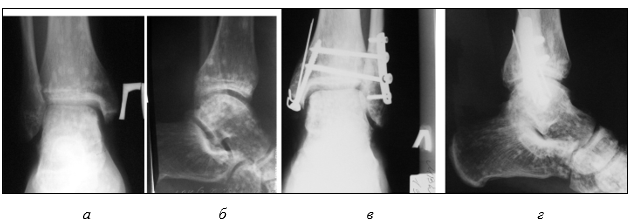

После контрольной рентгенограммы (рис. 1 а, б) выставлен диагноз: «Закрытый перелом внутренней лодыжки, краевой перелом заднего края большеберцовой кости, разрыв дистального межберцового синдесмоза, подвывих стопы кнаружи». В приемном покое под местной анестезией по Белеру произведена одномоментная ручная репозиция и наложена U-образная и задняя гипсовая иммобилизация (рис. 1 в, г).

Рис. 1 (архив автора). Пациент Г., 25 лет. Рентгенограмма в день обращения за медицинской помощью: до репозиции (а, б); после репозиции (в, г)

Учитывая то, что стояние после репозиции внутренней лодыжки было неудовлетворительным, после спадения отека, через 10 дней произведена операция: «Открытая репозиция наружной лодыжки, остеосинтез пластинкой, внутренняя лодыжка синтезирована винтом и деротационными спицами. Остеосинтез дистального межберцового синдесмоза позиционными винтами» (рис. 2 в, г).

Рис. 2 (архив автора). Пациент Г., 25 лет. Сравнительная рентгенограмма правого (а, б) и левого (после операции) голеностопного сустава (в, г)